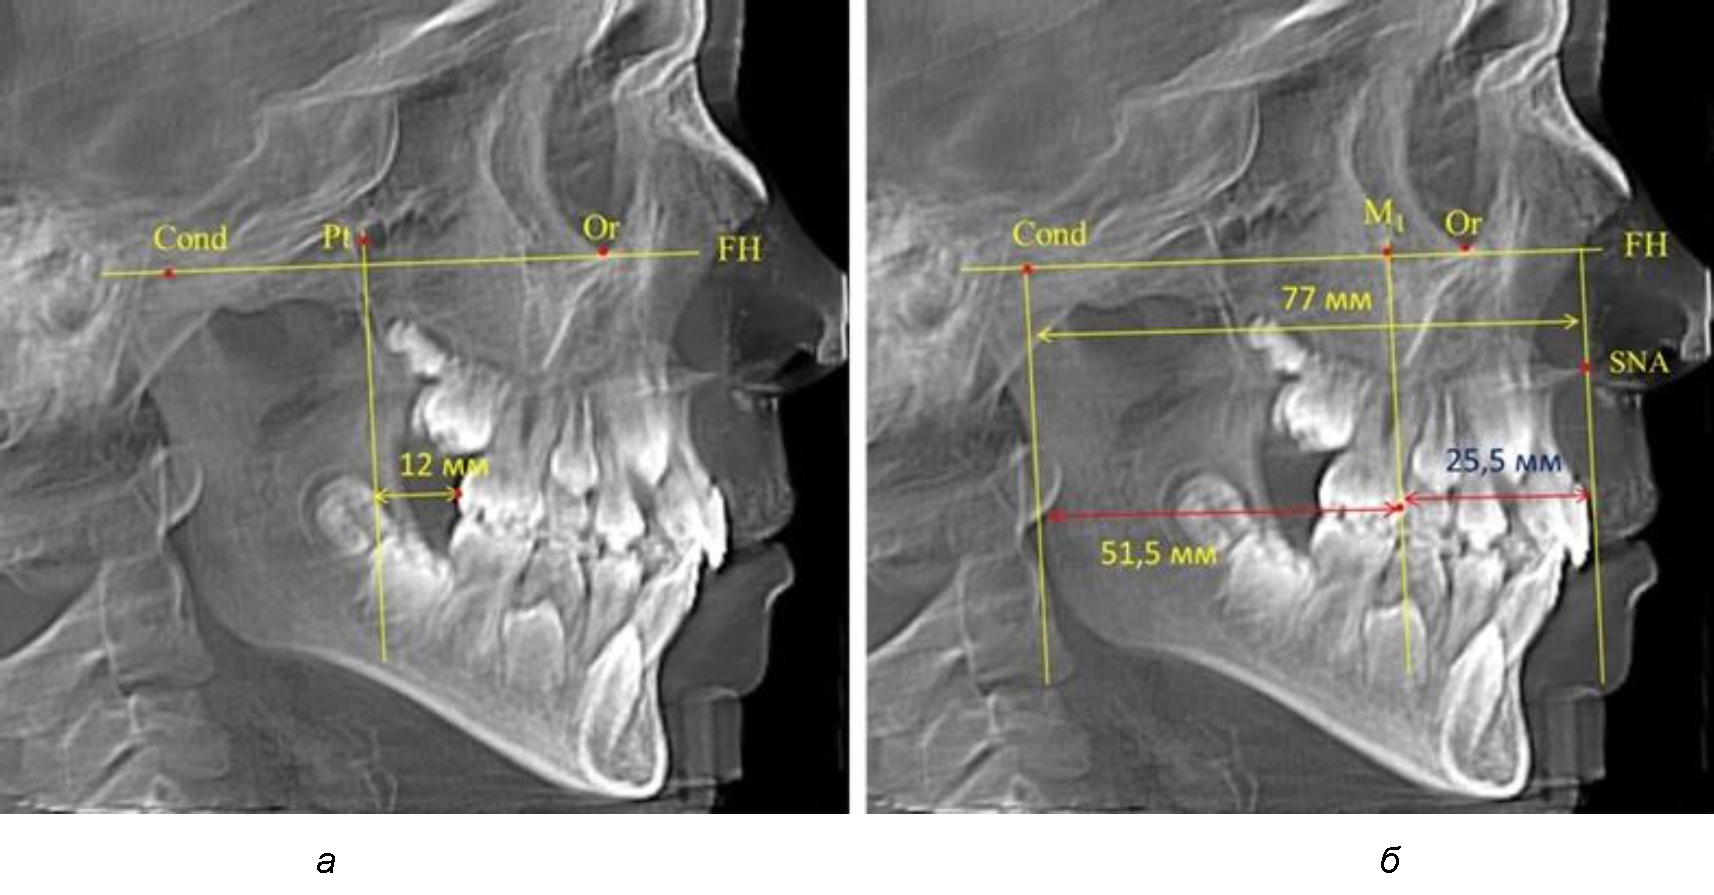

После прорезывания вторых постоянных моляров кондилярно-спинальный увеличивался до 80 мм.

Дистальная поверхность первого постоянного моляра отстояла от крыловидной вертикали на величину, составляющую около 18 мм, что, так же, как и в предыдущих периодах прикуса, было близким по значению к данным R. E. McDonald, а именно возраст, плюс 3 мм.

Обращает на себя внимание отношение глубины гнатического отдела лица к дистальному отделу, а именно к кондилярно-молярному расстоянию, которое, вне зависимости от сагиттальных размеров, составляло 1 : 1,5.

Рентгенограмма 16-летнего ребенка, с реперными линиями и анализируемыми линейными параметрами по двум используемым методам, представлена на рис. 6.

Рис. 6. Особенности положения первых моляров по R. E. McDonald (а) и по предложенному методу (б) у ребенка 16 лет